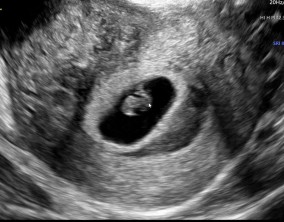

시험관 1차, 진짜 로또가 찾아왔어요